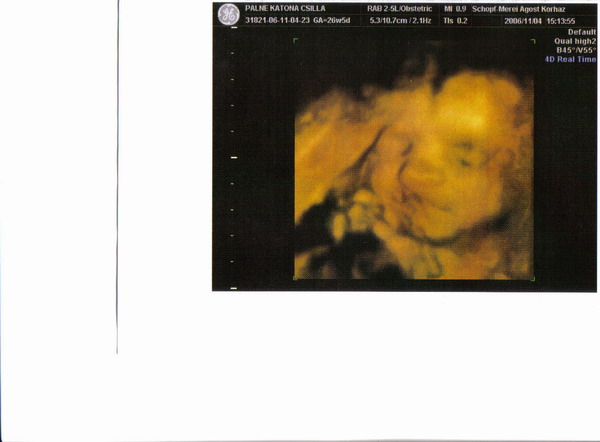

Uh-val az a helyzet, hogy nálunk kizárólag a megyei kórházban készült uh-t fogadják el hivatalosnak. Tehát, rá vagyok kényszerülve. Persze a 16. héten voltunk a magándokimnál "nemhivatalos" uh-n, és az nagy élmény volt. Azt azonban nem szeretném, hogy csak az én lelkecském miatt kétszer zaklassuk a babát (egy uh a rendelőben a mamának, egy uh a kórházban a kiskönyvbe). Lehet, azt mondjátok, hülye vagyok, és tudom, hogy semmi baja nem lesz, de akkor is úgy érzem, hogy utálja a gyerek. A megnyugtatásunk miatt azért még v.szeg elmegyünk egyszer pluszban a 24. hét körül.

De akkor már inkább 4D-re.